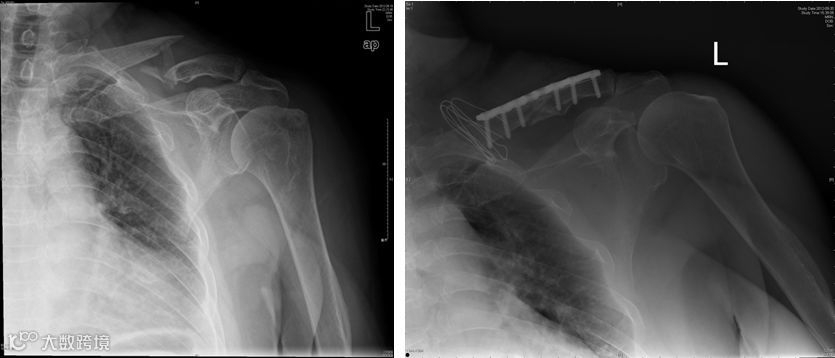

1、锁骨骨折

功能锻炼方法:

握拳、伸指、分指、腕屈伸、腕绕环、肘屈伸、前臂内外旋等主动练习,幅度尽量大,逐渐增加用力程度。

骨折后2周可增加捏小球,抗阻腕屈伸运动及被动或助力的肩外展、旋转运动等。

骨折后3周可增加抗阻的肘屈伸于前臂内外旋转;仰卧位,头与双肘支撑做挺胸练习。

骨折愈合解除外固定后,应开展全面练习肩关节活动练习:站立位上肢向患侧屈,做肩前后的摆动。

患肢上举爬肩梯,抗阻牵拉肩、肘屈伸练习。但在骨折2周内应避免做大幅度的肩内收与前屈练习。